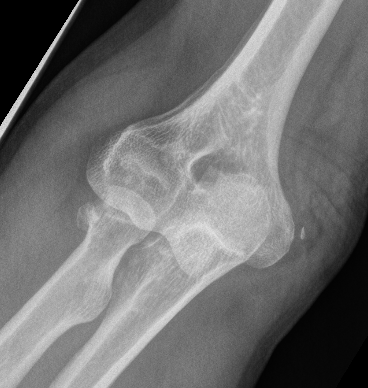

Elbow dislocation with radial head fracture

Management

Critical to elbow stability

Based upon Mason classfication